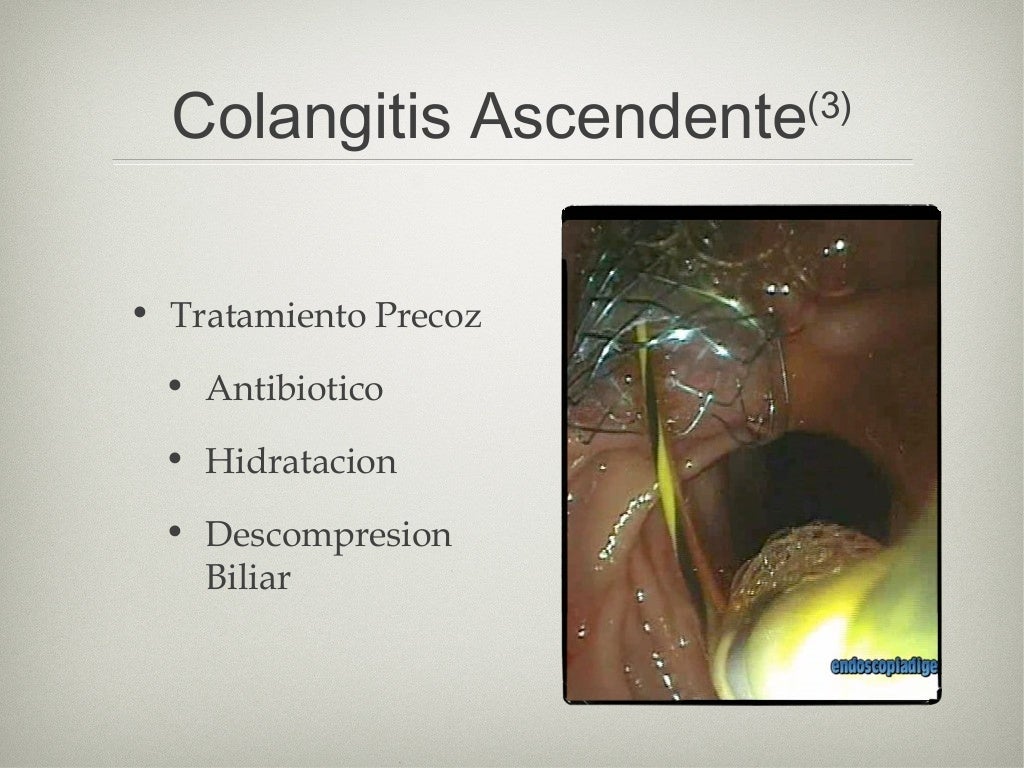

A missed case of intraabdominal sepsis BMJ Case Reports